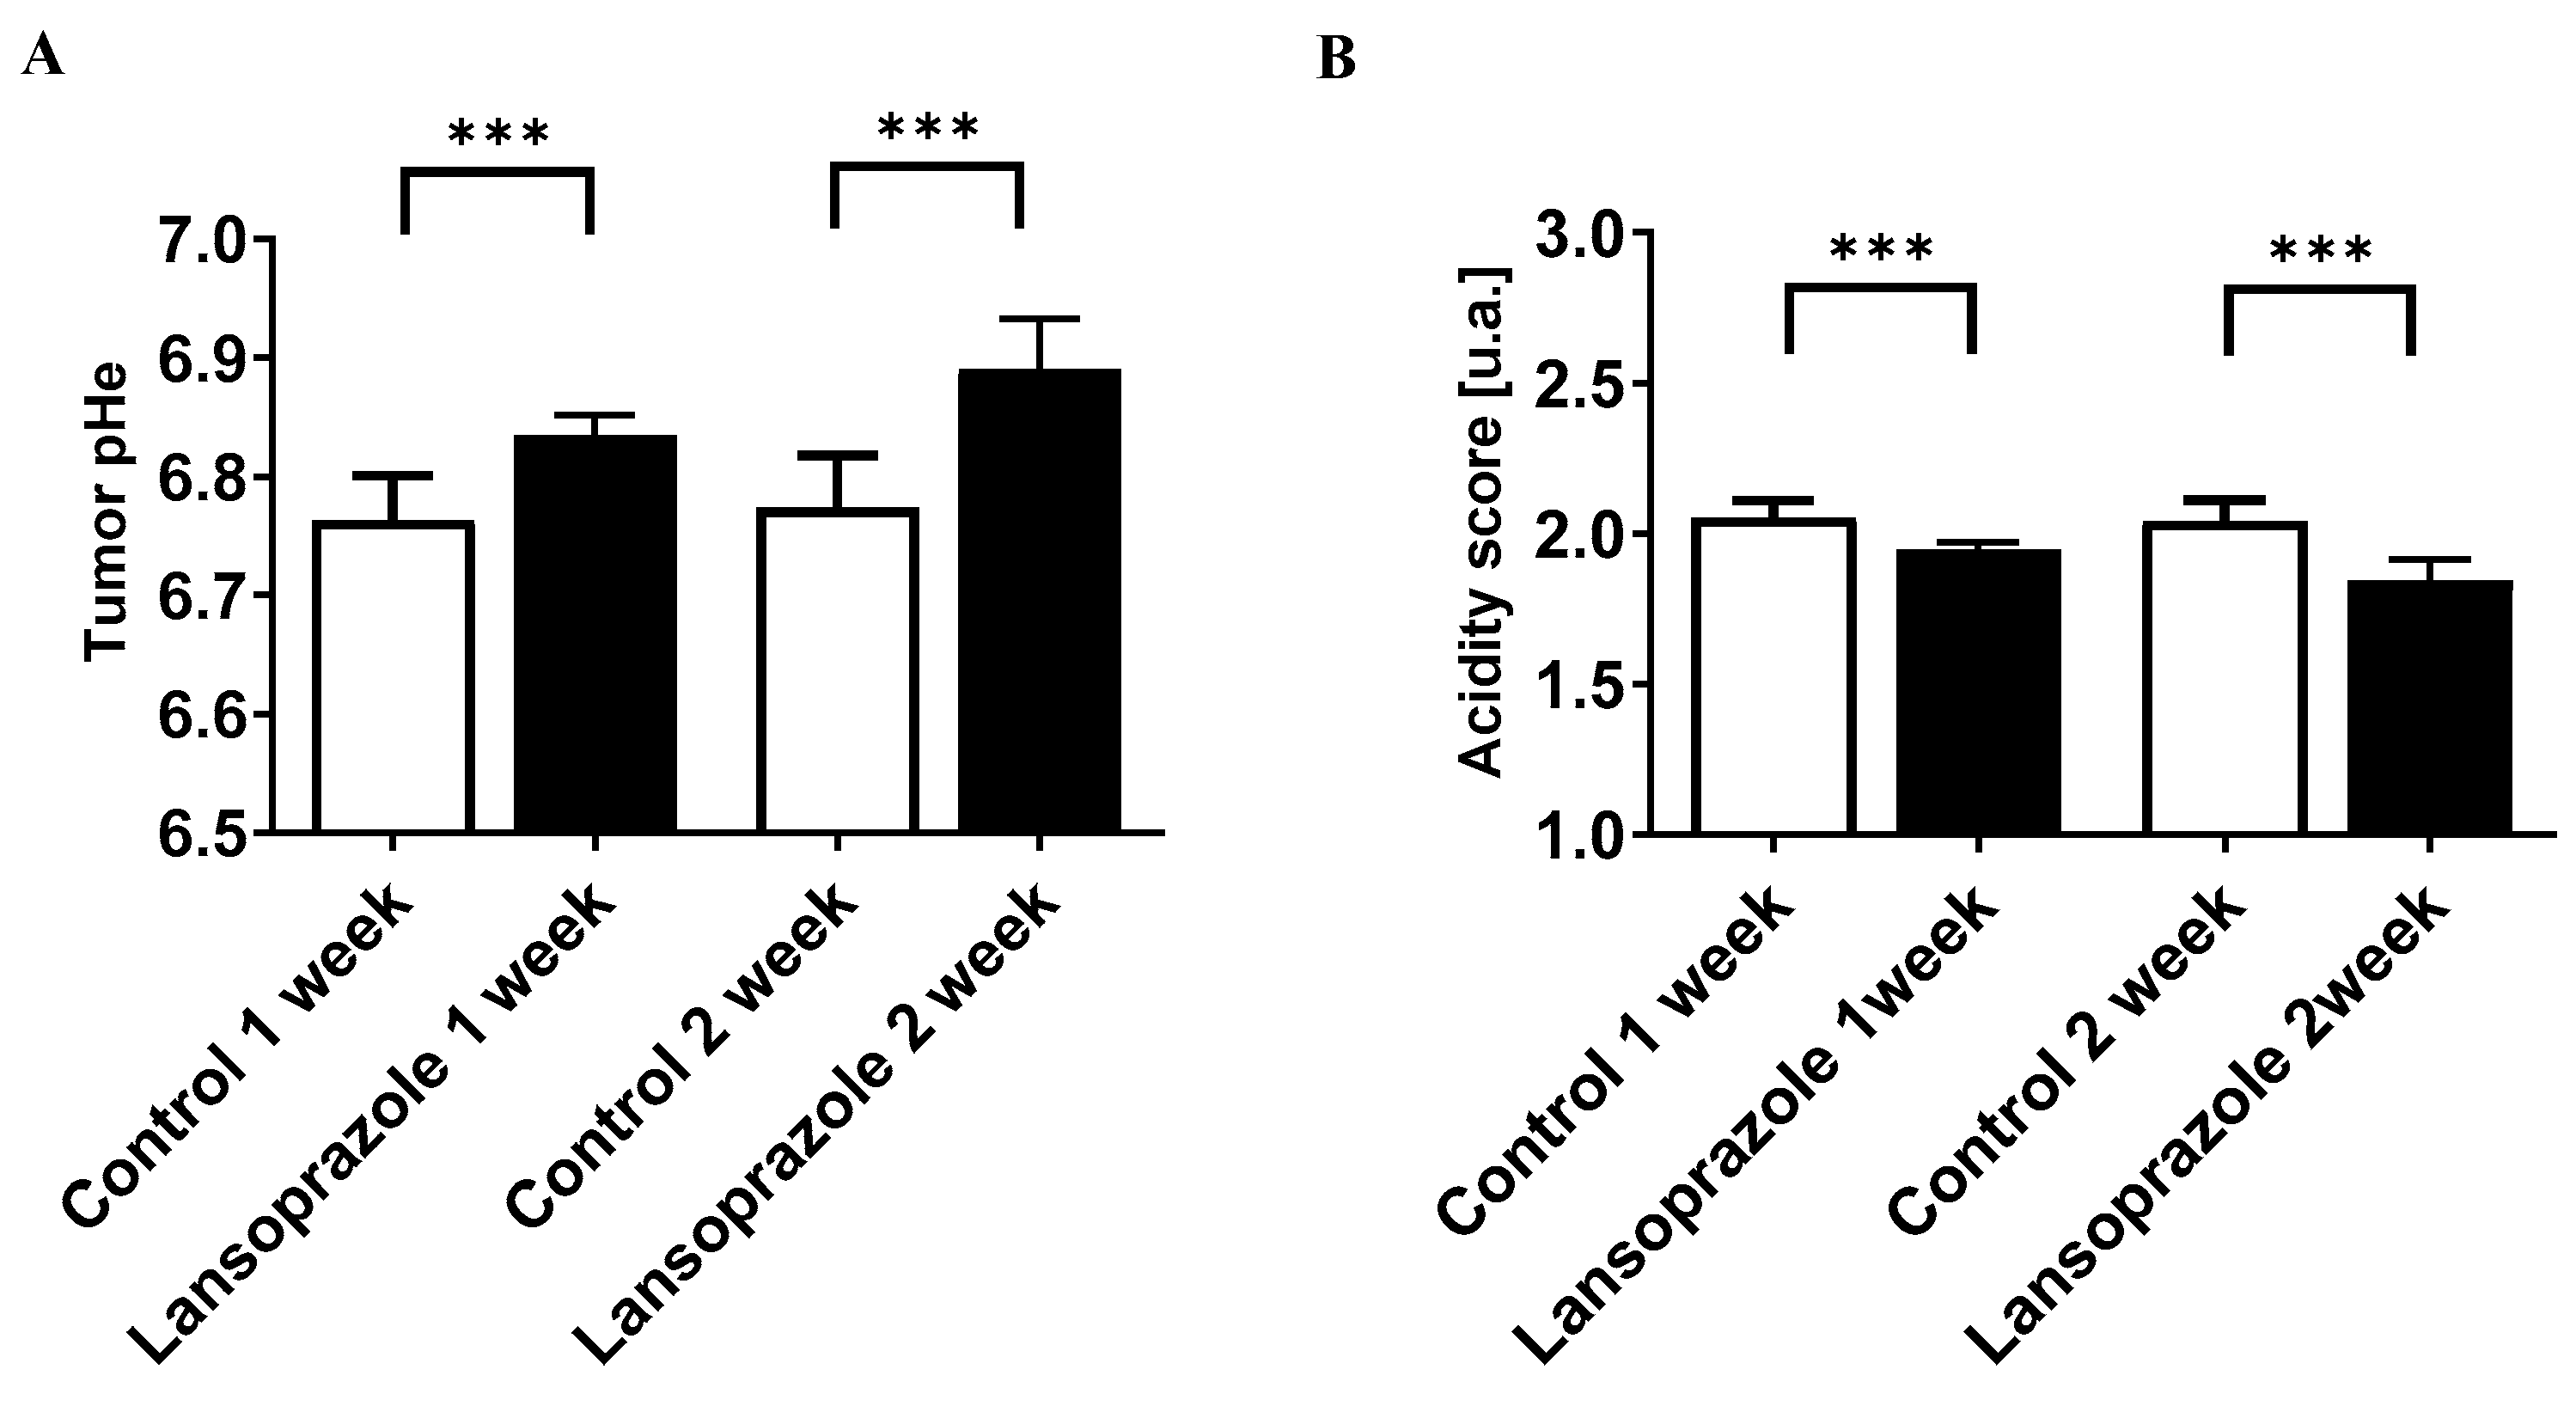

2.7. MRI-CEST Tumor pH Imaging and Analysis

3.5. Lansoprazole Exhibits Increased Extracellular pH In Vivo Assessed through MRI-CEST pH Imaging